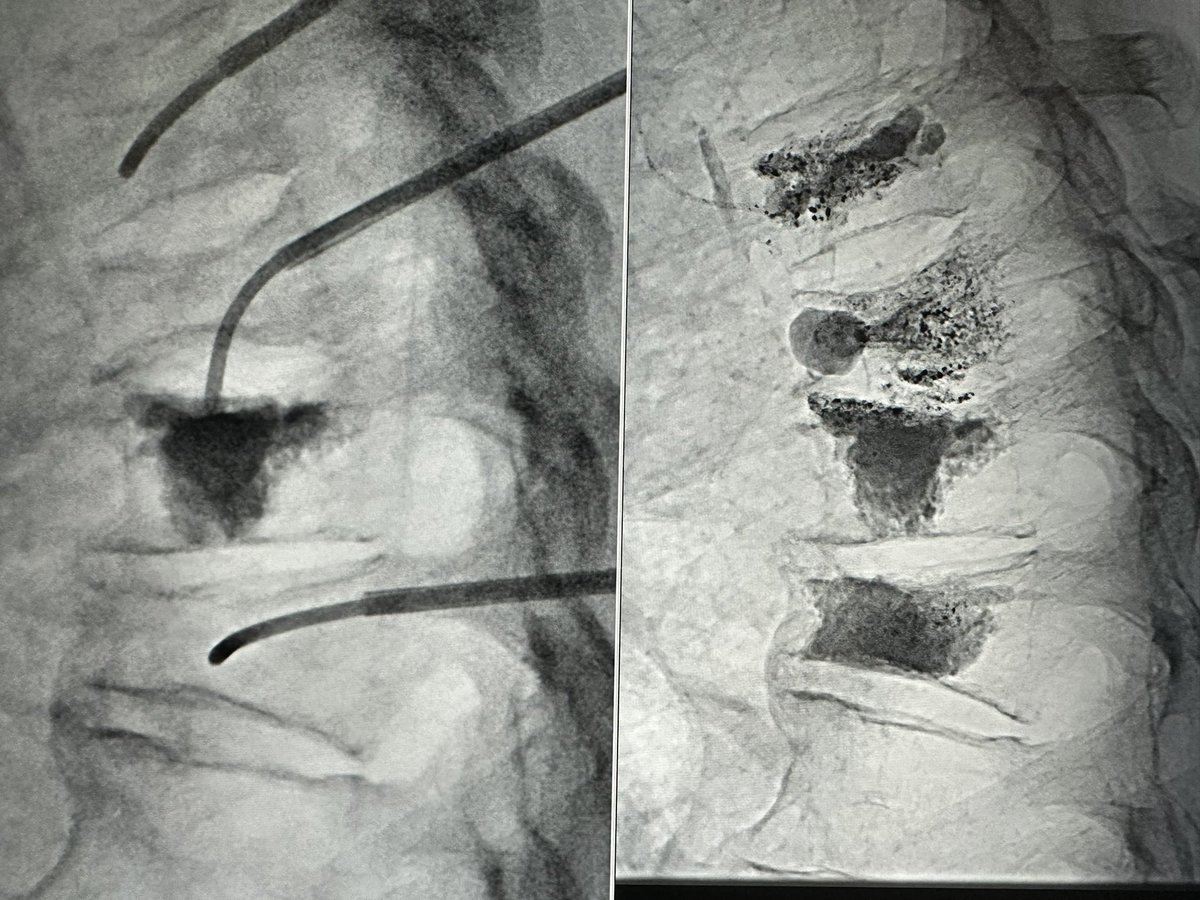

Chylous leak (4L daily) in neck s/p neck Sx. Thoracic duct fenestration and retrograde embolization Yale New Haven Health #irad SpfldClinic Society of Interventional Radiology BackTable Vascular and Interventional CIRSE The British Society of Interventional Radiology SIR RFS ISVIR India JVIR SIR ECS GEST -Global Embolization Symposium & Technologies @IR_juniors RSNA PAIRS U of MN Radiology